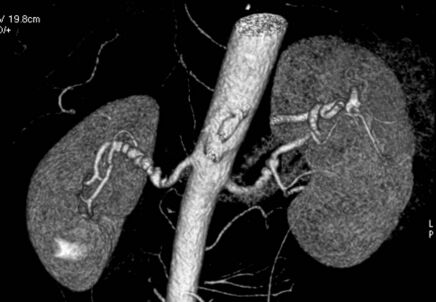

Volume rendered CTA of renal arteries in patient with medial fibromuscular dysplasia

Visualization of blood flow in the renal arteries (those supplying the kidneys) in patients with high blood pressure and those suspected of having kidney disorders can be performed using CTA. Stenosis (narrowing) of a renal artery is a cause of hypertension (high blood pressure) in some patients and can be corrected. A special computerized method of viewing the images makes renal CT angiography a very accurate examination.[6] CTA is also used in the assessment of native and transplant renal arteries.[3] While CTA is great for imaging of the kidneys, it lacks the ability to perform procedures at the same time. Thus traditional catheter angiography is used in cases of acute renal hemorrhage or acute arterial obstruction.[2]